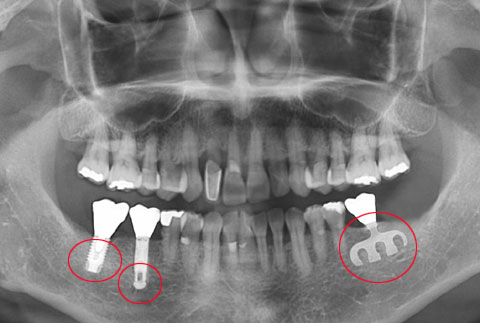

사진 왼쪽부터 현재 쓰는 임플란트, 15~20년전 쓰던 임플란트, 25~30년 전 쓰던 임플란트 치아를 현재 임플란트 시술을 받고 있는 환자의 엑스선 사진에 합성했다. / 에스플란트치과병원 제공

요즘 가장 많이 쓰는 임플란트는 스크류형인데, 스크류의 모양에 따라 분리형과 일체형으로 나뉜다.

분리형 임플란트는 예전부터 사용하는 기본적인 임플란트 시스템으로, 많은 형태의 임플란트 제품 중 시술 실패율이 가장 낮다. 임플란트를 뼈에 심고 필요한 기간 동안 잇몸 속에서 뼈와 결합이 이루어지도록 3~6개월 정도 기다린다. 임플란트와 뼈가 결합된 것이 확인되면 지대주라는 기둥을 연결하기 위해 잇몸에 조그만 구멍을 내서 길을 만드는 2차 수술이 필요하다. 분리형의 단점은 위의 설명처럼 수술을 두 차례 해야 한다는 것이다.

일체형 임플란트는 임플란트 본체와 나중에 연결하는 지대주가 하나로 연결돼 만들어진다. 분리형과 달리 추가 수술이 필요 없고, 임시 치아를 단기간 내에 연결할 수 있는 장점이 있다. 골질이 충분히 좋은 젊은 환자에게 더 적합하다. 그러나 아직 임플란트와 뼈가 충분히 결합되지 않은 상태에서 외부의 힘이 무리하게 가해지면 파손될 가능성이 있으므로 이식 뒤 상당 기간 주의해야 한다.